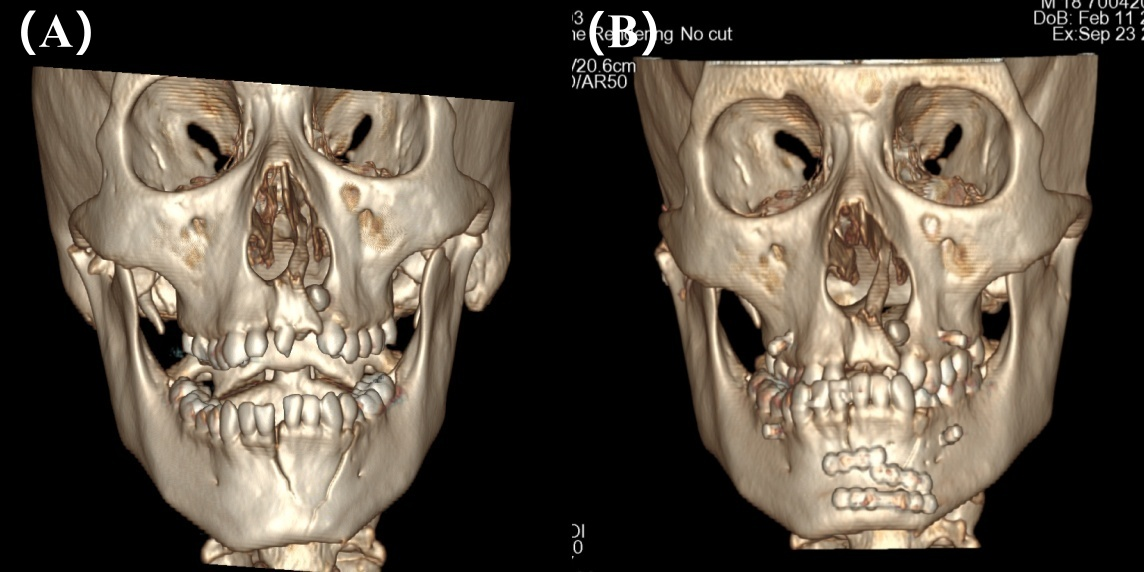

图1:颌面部CT三维重建冠状位影像(A)术前;(B)术后

图2:颌面部CT三维重建矢状位影像(A)术前;(B)术后